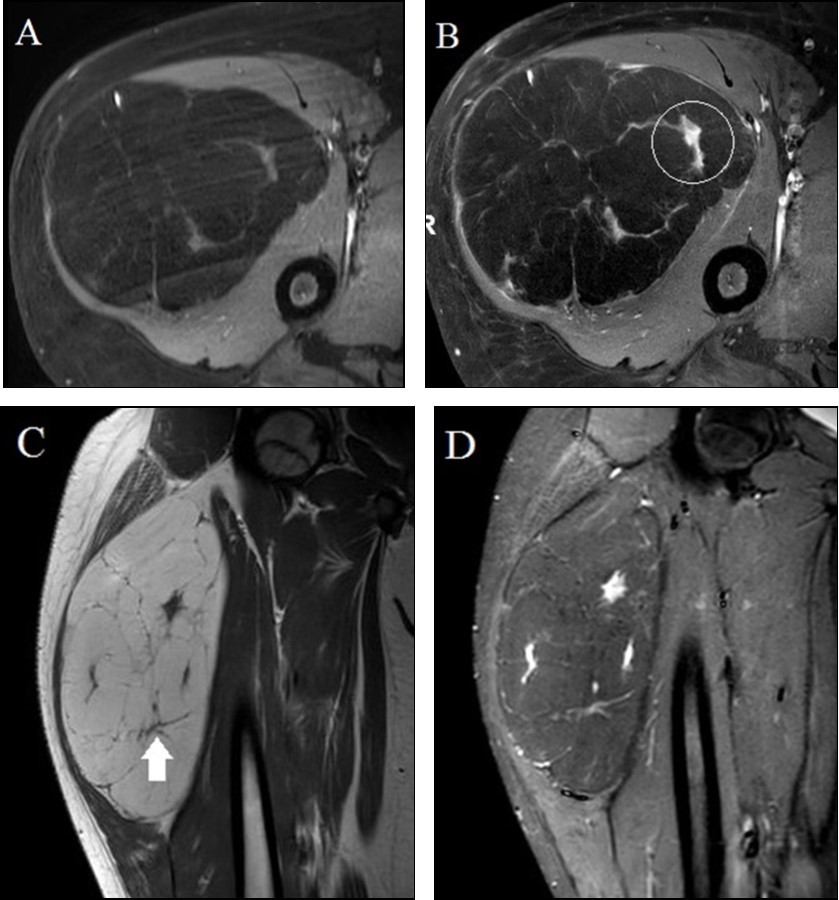

A 13 year old male presented to his local physician with a painless, slowly enlarging palpable mass of the proximal right thigh. Contrast-enhanced MRI was performed which raised concern for soft tissue sarcoma. We were consulted for a second opinion interpretation of the imaging study and recommendations for management. Outside multi-planar and multi-weighted MRI demonstrated a large lipomatous anterior compartmental thigh mass (Figure 1A-D). The mass was predominantly fatty with the majority of the tumor following the signal intensity of subcutaneous fat on both T1-weighted and fat-suppressed images. Internal enhancing nodularity (Figure 1B) and slightly thickened septations (Figure 1C) argued against simple lipoma and did initially raise concern for liposarcoma; however, liposarcomas are extremely rare in children. MRI findings of a slightly complex mostly fat containing mass with mild nodularity and thin internal septations are often seen in atypical lipomatous tumors. While greater than most reported lipoblastomas, patient age was felt to be more suggestive of lipoblastoma than ALT. Imaging features were not consistent with a simple purely fatty lesion such as lipoma and lack of any dominant internal non-adipocytic soft tissue elements argued against dedifferentiated liposarcoma. Under the care of an outside orthopedic surgeon, the patient underwent uncomplicated resection of the mass with negative margins and recovered well following surgery; gross tumor size and description of capsule at outside surgery are not available. Histopathology confirmed a lipomatous neoplasm with mature appearing white adipocytes lacking atypia or nuclear pleomorphism and several internal fibrous septae (Figure 2). Additionally, numerous interspersed multivacuolated brown fat cells with granular eosinophilic cytoplasm were identified yielding a final unexpected pathologic diagnosis of hibernoma.

Figure 1.13 year old male with a fatty proximal right thigh mass. A-B. Axial unenhanced (A) and gadolinium-enhanced (B) fat-suppressed T1-weighted turbo spin echo images demonstrate an anterior compartmental mass largely demonstrating similar signal intensity to subcutaneous fat with internal enhancing nodularity (circle in B). C-D. Coronal T1-weighted turbo spin echo (C) and short tau inversion recovery (D) images demonstrate internal thin internal septations (arrow in C) and internal nodularity with increased STIR signal intensity.